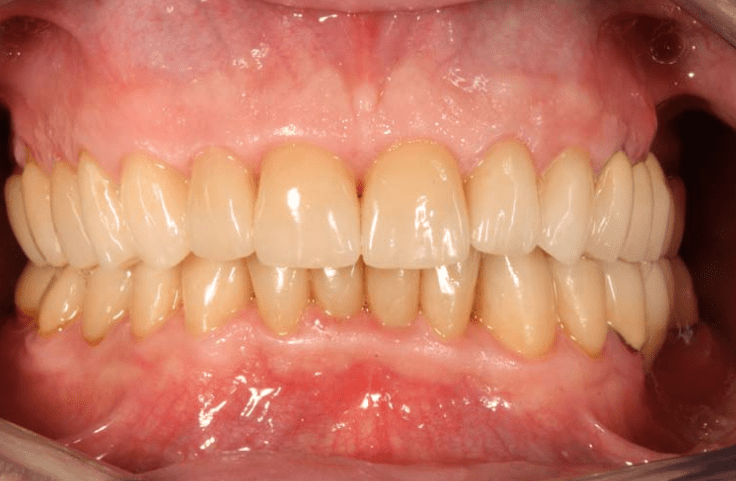

Ukázky zákroků

Podívejte se na konkrétní výsledky naší práce. Díky moderním postupům, preciznímu přístupu a zkušenému týmu dokážeme obnovit funkčnost i estetiku chrupu tak, aby výsledek odpovídal individuálním potřebám každého pacienta. Níže najdete reálné případy našich klientů – srovnání před a po.

MDDr. Petr Caha